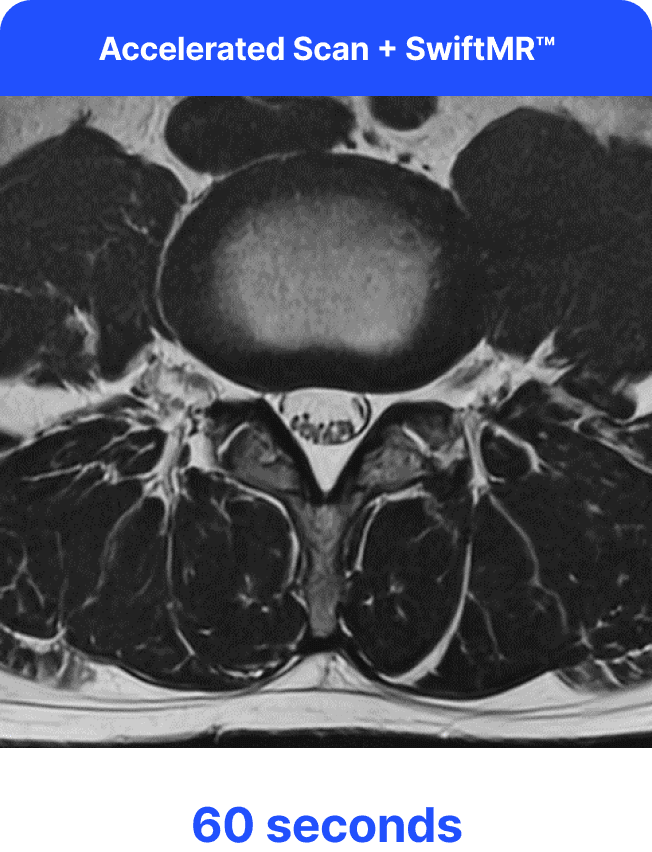

Το SwiftMR είναι μια λύση βαθιάς μάθησης που επιτρέπει τη μείωση του χρόνου σάρωσης MRI, ενισχύοντας την άνεση του ασθενούς χωρίς να θυσιάζει την ποιότητα της εικόνας. Η λύση επιτρέπει στα κέντρα ακτινολογίας να επιτύχουν νέα επίπεδα παραγωγικότητας και αποτελεσματικότητας, καθώς οι μικρότεροι χρόνοι σάρωσης αυξάνουν τη ροή ασθενών — ξεκλειδώνοντας ευκαιρίες για έσοδα και ανάπτυξη.

Η ομάδα μας θα βελτιστοποιήσει τα πρωτόκολλα MRI για να επιταχύνει τις σαρώσεις, παράγοντας αρχικά ταχύτερες αλλά χαμηλής ποιότητας εικόνες. Το μοντέλο βαθιάς μάθησης του SwiftMR στη συνέχεια χρησιμοποιείται για να βελτιώσει τις επιταχυνόμενες σαρώσεις, μετατρέποντάς τις αποτελεσματικά σε εικόνες υψηλής ποιότητας.